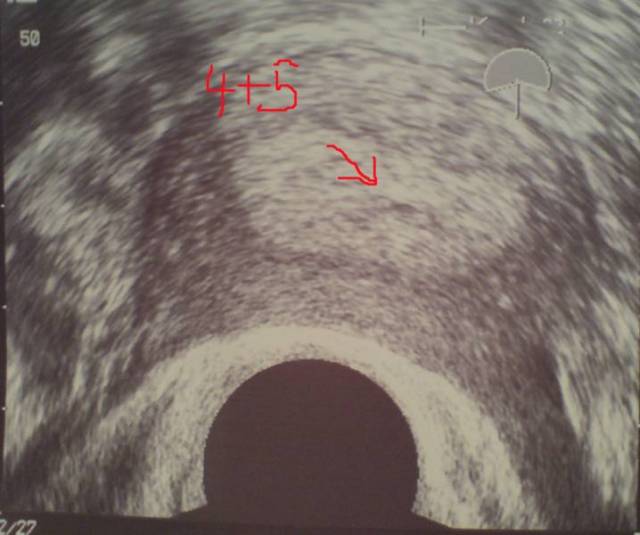

4+3 5. SSW Datum 19.05.2008 5. SSW